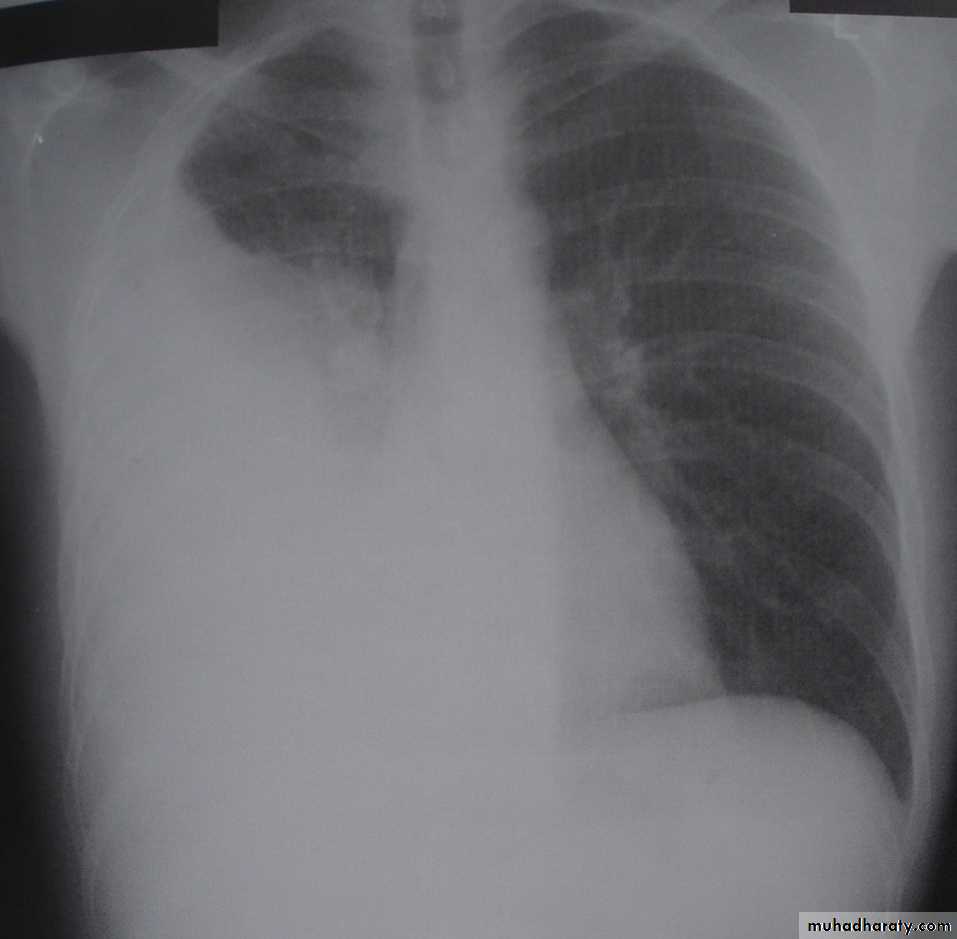

SLIDE NO. ((11))Female patient with history of asthma presented with severe dyspnoea and absence of breath sound on the left side

• What is the diagnosis?

• What immediate action you undertake?SLIDE NO. ((12)) Patient sustnained car accident. He has dyspnea, absence of breath sounds in the left side

• Diagnosis

• Your action• Indication for surgery